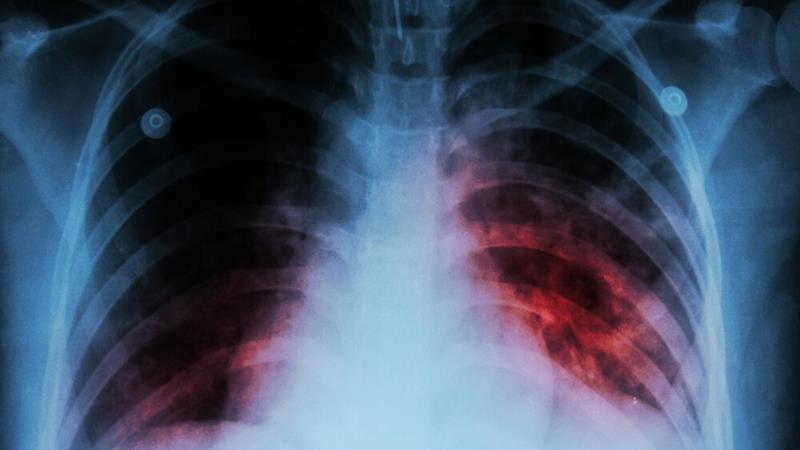

سالانه ۶ هزار نفر در کشور مبتلا به سل میشوند/چالش بهداشتی سل، همچنان ادامه دارد

ایسنا/ معاون بهداشتی دانشگاه علوم پزشکی ایلام با اشاره به آمار مبتلایان به بیماری سل گفت: سالانه بیش از ۶ هزار نفر مبتلا به سل فعال در کشور شناسایی و درمان میشوند.

به گزارش ایسنا و به نقل از روابط عمومی دانشگاه علوم پزشکی ایلام در روز پنجشنبه ۲۴ مهر، نیکونهاد با اشاره به علائم بیماری سل اضافه کرد: شاهعلامت ابتلا به سل ریوی، سرفه طولکشیده بیش از دو هفته است و باید جدی گرفته شود، تشخیص و درمان سل در مراکز بهداشتی کشور کاملاً رایگان است و همه افراد میتوانند از این خدمات بهرهمند شوند.